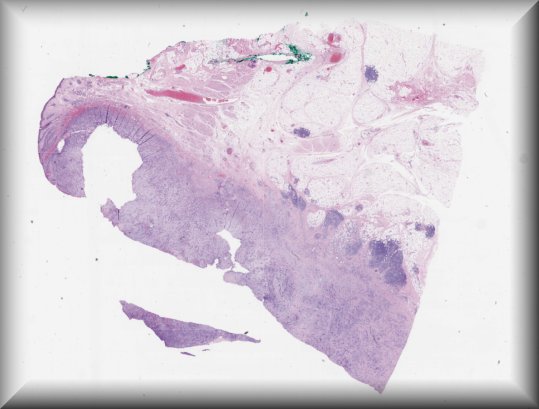

María Miguelina de la Garza Bravo (Houston): 53-year-old male with a 10-year-old history of bilateral exophthalmos (R>L), status post debulking. |